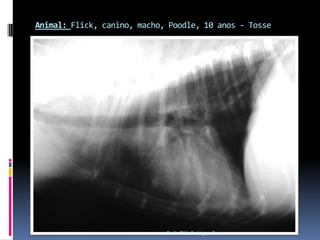

Animal: Flick, canino, macho, Poodle, 10 anos - TosseProfa. Tilde Rodrigues Froes

Animal: Flick, canino,macho, Poodle, 10 anos - TosseProfa. Tilde Rodrigues Froes